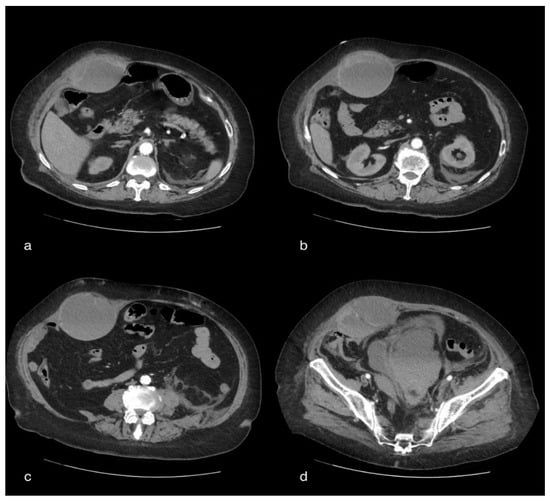

CT showed, bilaterally, the presence of multiple densitometric areoles of the GGO type with predominantly subpleural distribution with thickening of the interlobular septa with a “crazy paving” pattern. Lymphadenomegalies were observed in the mediastinum as well as ventilating phenomena. The volumetric increase in the right abdominal muscle of about 104 × 73 mm in the axial plane with a craniocaudal extension of about 28 cm, with inhomogeneous hypo/hyperdense densitometry, referred to as a hematoma, was reported. The pelvic excavation appeared to be occupied by a voluminous fluid/superfluid collection (dAP 20 cm × dcc 10 cm) spontaneously hyperdense in its most descending hematic part, appreciable in the context of two ecstatic vascular structures that were evident only in the portal and late phases of the study, compatible in the first hypothesis of venous bleeding. The uterus and the catheterized bladder appear to laterodeviate to the right. Further super-fluid collection with similar densitometric characteristics can be appreciated in the peri- and sub-renal site, posteriorly to the left with signs of hematic infarction of the ipsilateral psoas, which appears to have increased in volume. There was also a thin layer of pouring in the perihepatic area (Figure 3).

Figure 3. A 75-year-old female patient with volumetric increase in the rectus muscle of the right abdomen of approximately hypo/hyperdense inhomogeneous densitometry due to hematoma. The pelvic cavity appears to be occupied by a voluminous fluid/overfluid collection spontaneously hyperdense in its more declivity.

The clinical symptoms of rectus sheath hematoma are: nausea, vomiting, fever, abdominal and lumbar pain and abdominal tenderness on physical examination [30]. Early diagnosis and intervention are crucial in order to reduce patient mortality and morbidity. In 50% of rectus sheath hematoma cases, an evident hematoma is a useful sign. Imaging tests should be requested anyway in order to determine a differential diagnosis of rectus sheath hematoma in the case of abdominal pain. The diagnosis is confirmed by abdominal and pelvic CT scanning, which has a sensitivity of 100%. CT scan with IV contrast is deemed the gold standard for the identification of bleeding and in order to differentiate arterial and venous bleeds. A CT scan with contrast also provides information about contrast extravasation and all the intra-abdominal structures [31].